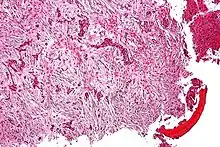

| Micrograph of an adamantinoma showing the biphasic histomorphology. H&E stain.. | |

Histologically, islands of epithelial cells are found in a fibrous stroma. The tumor is typically well-demarcated, osteolytic and eccentric, with cystic zones resembling soap bubbles.[2]